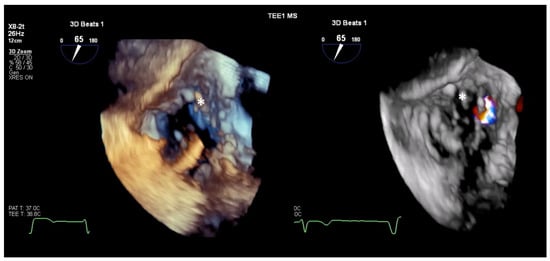

4.2. 3D Echocardiography

- Utsunomiya, H.; Harada, Y.; Susawa, H.; Takahari, K.; Ueda, Y.; Izumi, K.; Itakura, K.; Ikenaga, H.; Hidaka, T.; Fukuda, Y.; et al. Comprehensive Evaluation of Tricuspid Regurgitation Location and Severity Using Vena Contracta Analysis: A Color Doppler Three-Dimensional Transesophageal Echocardiographic Study. J. Am. Soc. Echocardiogr. 2019, 32, 1526–1537.e2. [Google Scholar] [CrossRef] [PubMed]

- Hahn, R.T. State-of-the-Art Review of Echocardiographic Imaging in the Evaluation and Treatment of Functional Tricuspid Regurgitation. Circ. Cardiovasc. Imaging 2016, 9, e005332. [Google Scholar] [CrossRef]